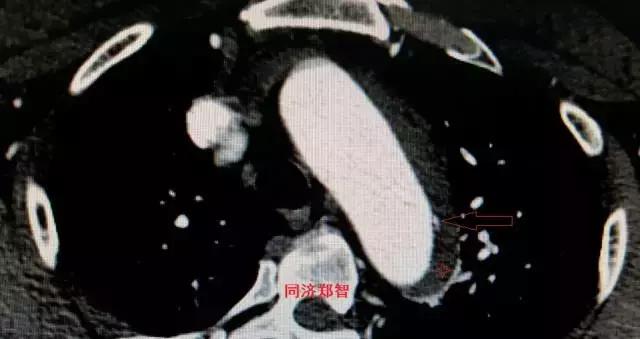

平扫CT提示降主动脉内膜片影(白箭头所示),CTA显示为B型主动脉夹层。